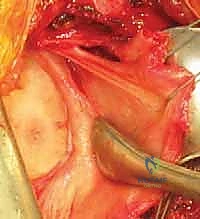

الخطوة 5: تثبيت وشد المحفظة السفلية (Inferior Capsular Shift)

في الحالات التي يعاني فيها المريض من ترهل شديد في محفظة المفصل (Capsular Redundancy)، لا يكفي إصلاح الشفا الحقاني وحده. يقوم أ.د. محمد هطيف بإجراء تقنية "الطي" أو الشد (Plication). يتم أخذ طيات من نسيج المحفظة المترهل وربطها مع الشفا الحقاني، مما يقلل من حجم المحفظة ويشدها مثل "البدلة المفصلة تفصيلاً"، مما يمنع أي مساحة زائدة قد تسمح للكتف بالانزلاق السفلي أو الأمامي.

الخطوة 6: الفحص النهائي وإغلاق الشقوق

يتم فحص المفصل ميكانيكياً بالمنظار للتأكد من استعادته للاستقرار الكامل وعدم وجود أي احتكاك غير طبيعي. بعد ذلك، تُسحب الأدوات وتُغلق الشقوق الصغيرة بغرز تجميلية.